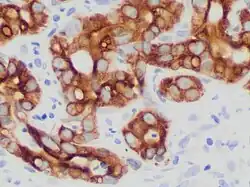

Histologically, cholangiocarcinomas may vary from undifferentiated to well-differentiated. They are often surrounded by a brisk fibrotic or desmoplastic tissue response; in the presence of extensive fibrosis, it can be difficult to distinguish well-differentiated cholangiocarcinoma from normal reactive epithelium. There is no entirely specific immunohistochemical stain that can distinguish malignant from benign biliary ductal tissue, although staining for cytokeratins, carcinoembryonic antigen, and mucins may aid in diagnosis.[47] Most tumors (>90%) are adenocarcinomas.[48]

Pathology

Histologically, cholangiocarcinomas are classically well to moderately differentiated adenocarcinomas. Immunohistochemistry is useful in the diagnosis and may be used to help differentiate a cholangiocarcinoma from hepatocellular carcinoma and metastasis of other gastrointestinal tumors.[66] Cytological scrapings are often nondiagnostic,[67] as these tumors typically have a desmoplastic stroma and, therefore, do not release diagnostic tumor cells with scrapings.

- ^ Image by

Mikael Häggström, MD. Source for caption:

- Nat Pernick, M.D. "Cytokeratin 19 (CK19, K19)". Pathology Outlines. Last author update: 1 October 2013 - ^ Länger F, von Wasielewski R, Kreipe HH (July 2006). "[The importance of immunohistochemistry for the diagnosis of cholangiocarcinomas]". Der Pathologe (in German). 27 (4): 244–50. doi:10.1007/s00292-006-0836-z. PMID 16758167. S2CID 7571236.